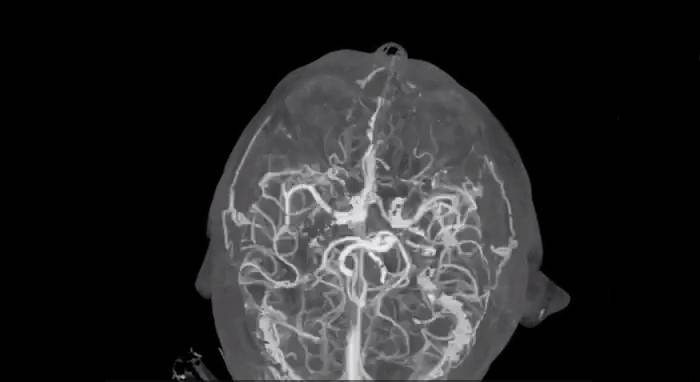

В Челябинске онкологи лечат опухоли кожи на «нулевой» стадии

Медицина